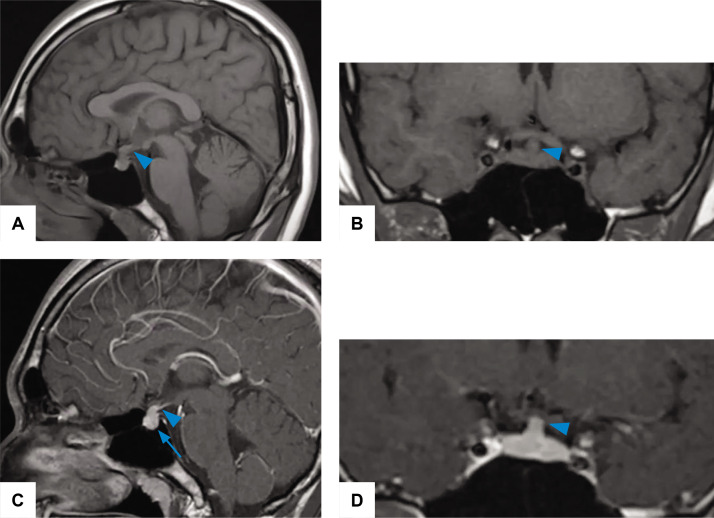

Lymphocytic hypophysitis (LHy) is a rare autoimmune inflammatory process that selectively affects the neurohypophysis and infundibulum, typically presenting with arginine vasopressin deficiency (AVP-D). On magnetic resonance imaging (MRI) with contrast, there is a thickening of the pituitary stalk, enlargement of the neurohypophysis or both with homogeneous enhancement. LHy can be self-limiting and regression can be seen radiologically during follow-up. A 22-year-old male presented with clinical findings consistent with AVP-D in 2016. MRI brain demonstrated enlargement of the pituitary stalk and absence of a posterior pituitary bright spot. He was given a trial of glucocorticoid treatment. His serial MRI brain showed a reduction of the pituitary stalk, but the AVP-D persisted. He was diagnosed with LHy. LHy is characterized by lymphocytic infiltration, leading to eventual destruction of the pituitary tissue accompanied by varying degrees of pituitary dysfunction. Definite diagnosis can only be established via pituitary stalk biopsy. Due to the wide range of possible aetiologies, close monitoring is strongly recommended for the treatment of presumed cases lacking histopathologic confirmation. The response rate to glucocorticoids has been variable. Periodic monitoring of anterior pituitary function and pituitary MRI are essential in the management of this condition.